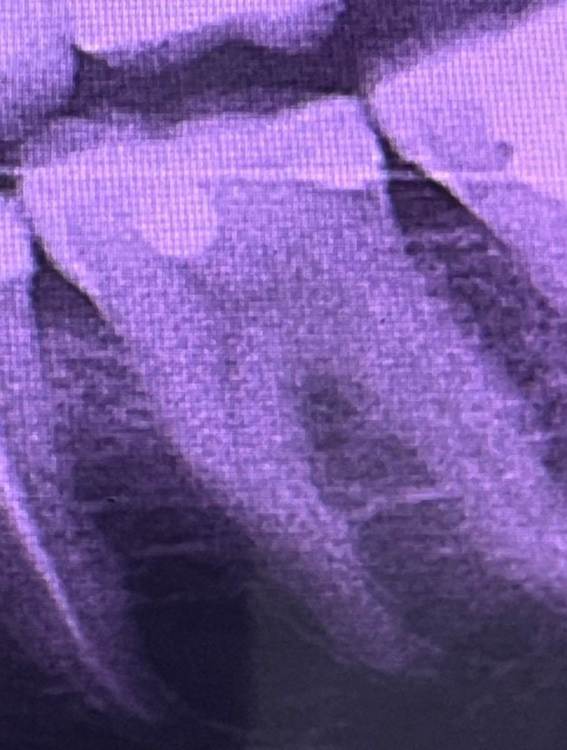

mateyko_69 Опубликовано 12 ноября, 2023 Поделиться Опубликовано 12 ноября, 2023 Здравствуйте, дорогие врачи! Хочу задать вам вопрос касательно лечения моей «шестерки», к сожалению врач не говорит на русском, поэтому его объяснение могу лишь поверхностно объяснить тут. Шестерка была с глубоким кариесом, который не было видно внешне. Зуб оставили живым, поставили пломбу и я пошел домой. После, я начал чувствовать что появляется не сильная боль, когда кусаю что нибудь твердое именно этим зубом, также есть небольшая чувствительность от горячего/холодного. Зуб не ноет, не болит без какого либо воздействия. То есть только, если на него надавить чем то действительно твердым. Я задал вопрос врачу, почему так? Он ответил, что зуб ещё не требовал лечения каналов, поэтому он под пломбу поставил какой-то «лекарство», поэтому боль может оставаться несколько недель. но вот прошло уже две недели, а зуб все ещё реагирует. Поэтому задаюсь вопросом, стоит ли уже начинать что то делать, либо же пока ждать ещё какое-то время. Снимки до/после также добавил. Спасибо! Ссылка на комментарий

Carioznik Опубликовано 12 ноября, 2023 Поделиться Опубликовано 12 ноября, 2023 Здравствуйте, похоже на дебондинг пломбы ( отклеивание небольшого участка плобы на дне зуба). Понаблюдайте несколько недель. Если не пройдет, то эта проблема исправляется переделкой пломбы 1 Ссылка на комментарий